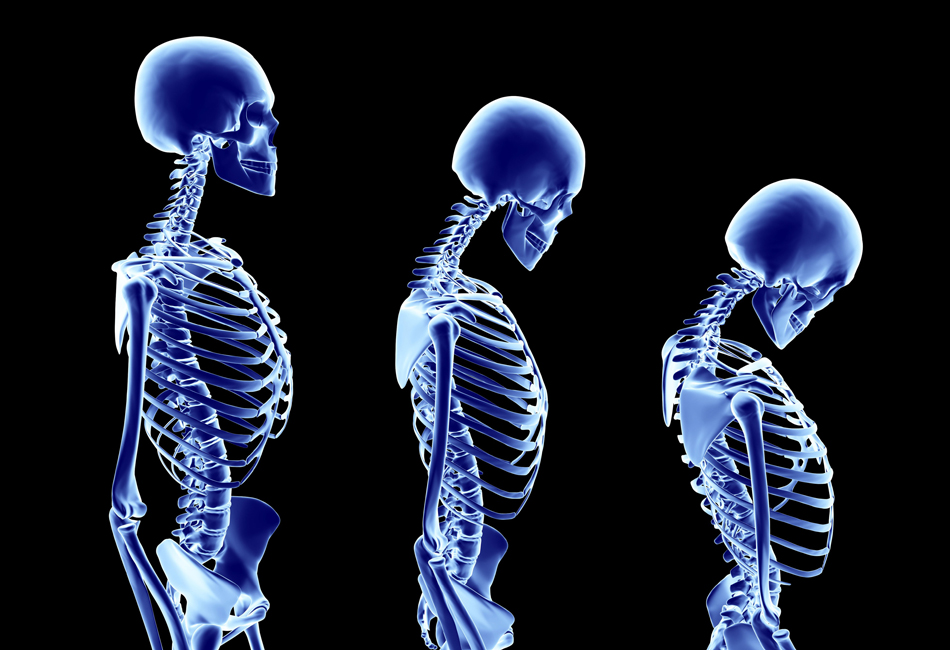

Científicos de todo el mundo van tras las pistas de la estatura, un rasgo mucho más complejo de lo que se creía, a juzgar por las más de mil variables genéticas involucradas en la altura humana, aunque solo se han identificado unas 180. La última (HMGA2) es responsable de cerca de un 1% de nuestra talla, es decir, de 0,3 a 1,4 cm, según la mayor o menor presencia de esta variante. Además del patrimonio genético, responsable del 90% de la altura, en el crecimiento interactúan otros factores ambientales, socioculturales y nutricionales. En los últimos 150 años se ha observado una tendencia a ser cada vez más altos y a tener pubertades más tempranas. Bien decía el pediatra británico James Tanner que la estatura es “el espejo del nivel de vida de las poblaciones”. Nunca se había observado un impacto tan inmediato de la salud sobre la estatura como al comprobar cómo un episodio de diarrea hacía decaer la curva de crecimiento para recuperar su percentil después de un período de correcta nutrición.

Como indica la endocrinóloga Ángela Ferrer, del centro médico Teknon: “Aunque el crecimiento está determinado genéticamente, su desarrollo óptimo precisa aporte nutricional completo y equilibrado, y un ambiente psicosocial y sociocultural favorable”. España pegó el estirón en las últimas décadas del siglo XX. Hasta 10 cm, según un reciente estudio del Consejo Superior de Investigaciones Científicas (CSIC). Un hombre nacido en 1910 se quedaba en una media de 1,66 m (1,55 m en mujeres), mientras que los nacidos en 1987 han alcanzado 1,77 m; la mujer, 1,62. En ellas, la estatura media de las nacidas entre 1939 y 1958 sufrió un estancamiento que pudo deberse a las condiciones de la guerra, o incluso al estrés.

Las opciones son varias. La principal, la hormona del crecimiento, muy eficaz en caso de que haya un déficit total o parcial, aunque el gran reto está en los niños de talla baja familiar sin déficit de hormona de crecimiento; “pero la mayoría de los países no aprueba su uso de forma estandarizada”, aunque varios estudios los apoyan, indica la doctora. También se podría intervenir si queda crecimiento en el hueso, algo que se valora con un estudio de maduración ósea. Mientras los cartílagos de crecimiento estén abiertos, se puede crecer, independientemente de la edad cronológica del niño. ¿Y los complejos? La psicóloga asturiana Isabel Menéndez Benavente resta crédito a los estudios que tantas ventajas brindan a los altos, ya que no están suficientemente avalados: “Una estatura diferente, bien por defecto o por exceso, puede compensarse con una adecuada educación emocional”.